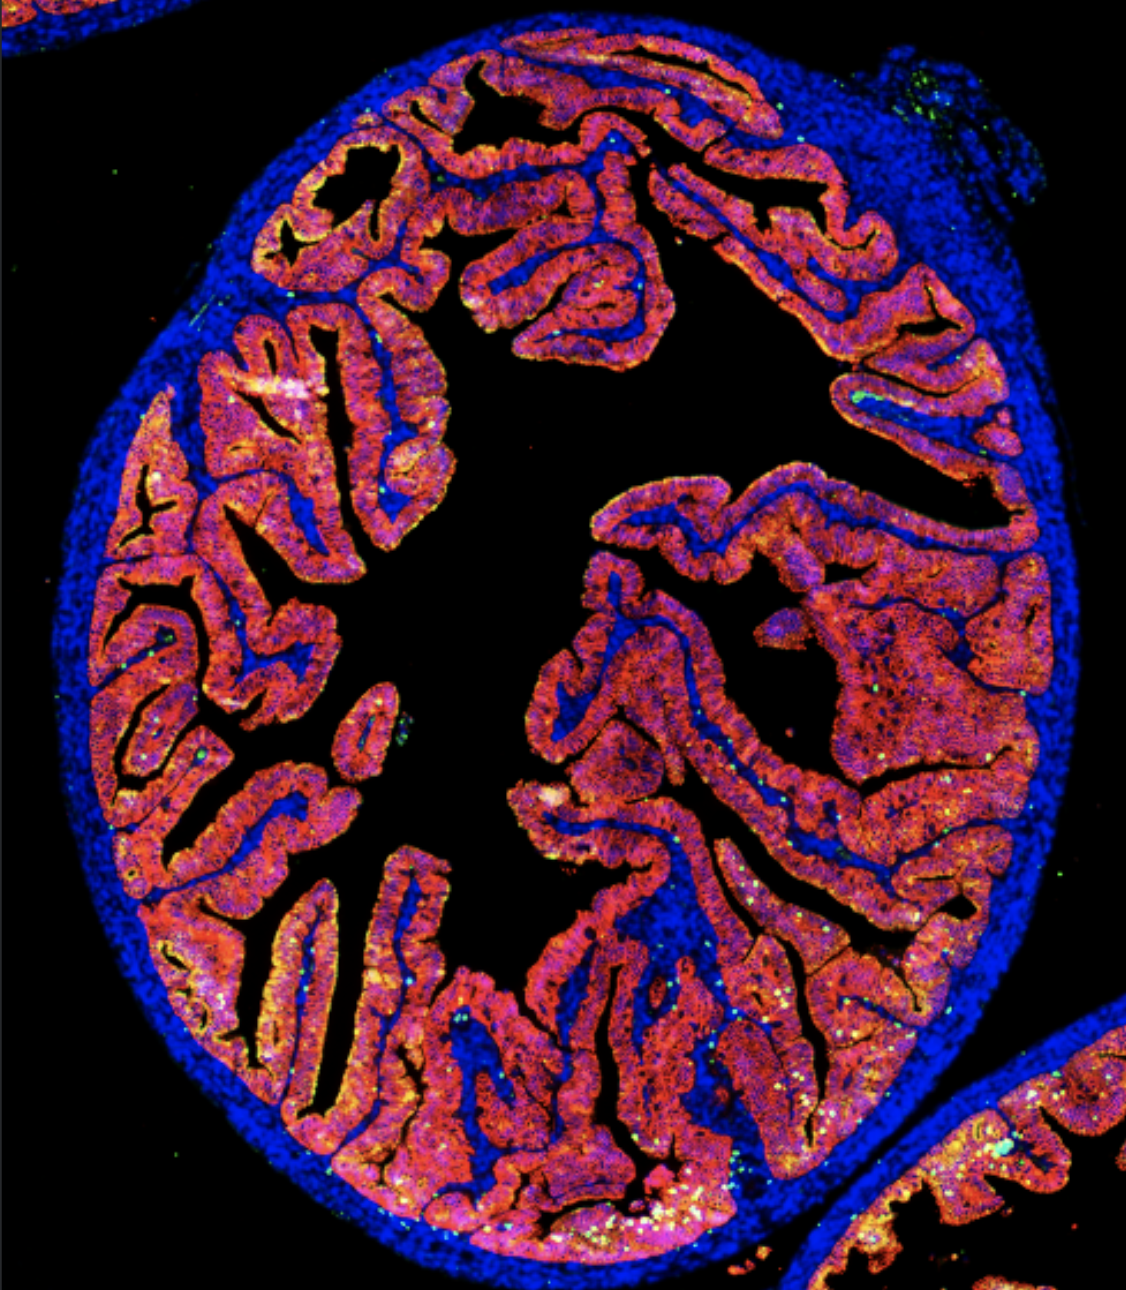

Work in the Erlebacher laboratory lies at the intersection of immunology and developmental biology. In particular, we are interested in how the developmental properties of a tissue influence its ability to mount a successful immune response, and, conversely, how cells of the immune system influence tissue development and remodeling. The main platform for our research is the mouse uterus. This organ is not only a simple mucosal tissue amenable to extensive experimental manipulation, but its ability to accommodate the presence of immunologically foreign tissues during pregnancy (i.e. the fetus and placenta) provides a striking example of how the anatomical organization and developmental plasticity of a tissue determines its immunological properties. Moreover, reproductive success relies upon the immunological protection afforded the fetus and placenta by the uterus, with insight into how this process breaks down having implications for disorders of human pregnancy, including spontaneous abortion, intrauterine growth restriction, preeclampsia, and preterm birth. We also study how the parenchymal cells of the uterus, through their specialized developmental and epigenetic properties, determine pregnancy outcome independently of their effects over immune cells. Lastly, we study how the uterine adaptation to pregnancy finds parallels in the adaptations of the tumor microenvironment that facilitate tumor escape from immune destruction.